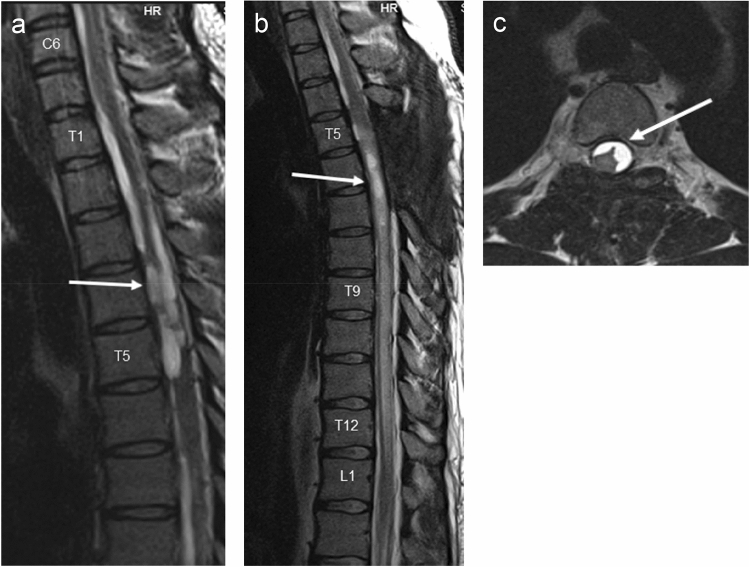

G.W., female, with a known history of ventriculoperitoneal shunting due to an internal hydrocephalus (18th September 2015), spinal canal tumor resection at the T7–T8 level (benign schwannoma) and a radical right-sided mastectomy due to breast cancer in October 2016. The woman was on systemic cancer treatment consisting of ACP + trastuzumab and hormonal therapy. During her stay at the Oncology Unit of our hospital (May 2017) patient experienced acute weakness of lower extremities. Reviewed by neurologist consultant the evidence of pyramidal paraparesis with bilaterally positive Babiński sign and superficial sensation impairment down from the T4–T5 level was found. A thoracic spine MRI revealed focal ischemic lesions—first of them of about 3 cm of length localised between levels T5 and T6 s and the second one of similar size at the T7–T8 level (benign schwannoma—due to its benign nature no adjuvant chemo or radiotherapy was performed) with a concomitant oedema of the spinal tissue. Also spinal canal presented a multi-level, thecal sac deformity with formation of fluid collections at C7–T1 and T12–L3 levels. The lesions were causing compression and deformation of neural structures in the spinal canal (Fig. 3)—with clinical picture indicating the diagnosis of adhesive arachnoiditis. The chemotherapeutic treatment was modified in aim to reduce its neurotoxicity. Despite the therapy and rehabilitation no improvement was noticed—the patient continued to mobilise with a wheelchair.

Fig. 3.

MRI T2-weighted STIR-sagittal view of spine board strict adhesion of the spinal cord to the dura mater in the thoracic spine with complete reduction of front fluid collection of the thecal sac. Numerous adhesions of pia mater with cystic lesions in the front part of the spinal canal at the cervicothoracic and thoracolumbar junction